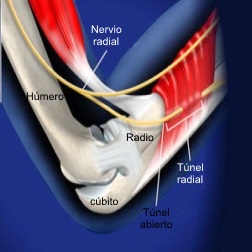

Síndrome del túnel radial

Este diagnóstico es muy controvertido

y se piensa que es el resultado del uso excesivo. Algunos autores

creen que el síndrome del túnel radial puede representar un síndrome

temprano de la compresión del nervio interóseo posterior (rama

profunda del nervio radial). Los sitios de compresión incluyen las

bandas fibrosas insertadas a la articulación radiocapitelar, vasos

recurrentes radiales, el origen tendinoso del extensor radial corto

del carpo, el origen tendinoso del supinador (es decir, arcada de

Frohse), y engrosamientos fibrosos dentro y en el margen distal del

supinador.

Síndrome del túnel radial

Síndrome del túnel radial se caracteriza por dolor

urente o quemante en la parte proximal anterolateral del antebrazo

en la región del cuello radial. Este síndrome suele aparecer en

personas cuyo trabajo requiere la extensión del codo repetitivo o la rotación del

antebrazo. La sensibilidad máxima se encuentra a 4 dedos distal al

epicóndilo lateral, en comparación con la epicondilitis lateral, en

el que el máximo dolorimiento está por lo general directamente sobre

el epicóndilo. Los síntomas se intensifican mediante la extensión

del codo y la pronación del antebrazo. Además, la supinación activa

resistida y la extensión del dedo largo causa dolor. generalmente no

hay debilidad y adormecimiento.